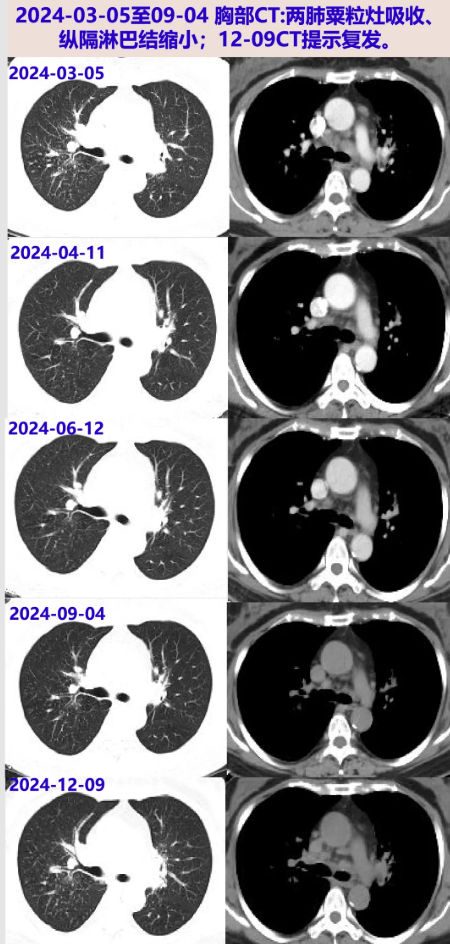

2024-03-05 胸部CT:右肺中叶节段实变不张,两肺多发结节(多发粟粒样改变),两肺慢性炎症,两肺门及纵隔、两侧颈根部-锁骨区多发肿大淋巴结;血常规:WBC 5.88×10^9/L,N 54.9%。无发热盗汗消瘦、咳嗽咳痰、呼吸困难、胸痛等。

2024-04-11 胸部CT:两肺炎症、纵隔淋巴结肿大较前片明显好转。继续甲泼尼龙20mg qd ×1周(共2周),后续减量方案:16mg qd×2周、14mg qd×2周、12mg qd×2周。

2024-06-12 淋巴结、灌洗液分枝杆菌培养(2024-03-07采样):阴性。胸部CT:两肺炎症病灶明显吸收,纵隔淋巴结明显缩小,较04-11相仿;复查炎症标志物、ACE阴性。当前甲泼尼龙10mg qd,后续每2周减量2mg至停药。

2024-08-26 停用甲泼尼龙。09-04胸部增强CT:两肺门及纵隔多发小及增大淋巴结,较06-12片部分稍大。继续停药。

2024-12-09 胸部CT:纵隔及肺门多发淋巴结肿大,两肺多发病变,均较09-04片进展;ACE阴性。考虑结节病复发,再次启动糖皮质激素治疗,方案:甲泼尼龙32mg qd×1周、28mg qd×2周、24mg qd维持。

2025-01-22 胸部CT:较24-12-09片肺内病灶吸收,纵隔淋巴结缩小。激素减量方案:甲泼尼龙20mg qd×3周、16mg qd维持。

2025-04-16 胸部CT:较前片好转(最大淋巴结位于左下气管旁19×14mm);炎症指标、ACE阴性;目前甲泼尼龙16mg qd,后续减量方案:14mg qd×2月、12mg qd×2月。

2025-08-14 胸部CT:较前片相仿。后续减量方案:10mg qd×2月、8mg qd×2月。

2025-12-17 胸部CT:较前片相仿。继续甲泼尼龙8mg qd,2~3月后复查胸部CT。